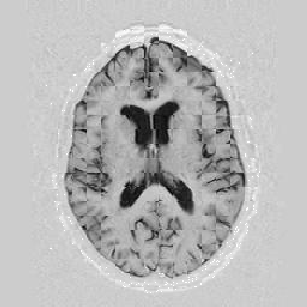

The results are shown for another pair of images in Figure [*].

Figure: Multi-scale NRR. From left to right, top then bottom: before NRR; after 5 iterations of NRR at level 2; after another 5 iterations of NRR at level 1.